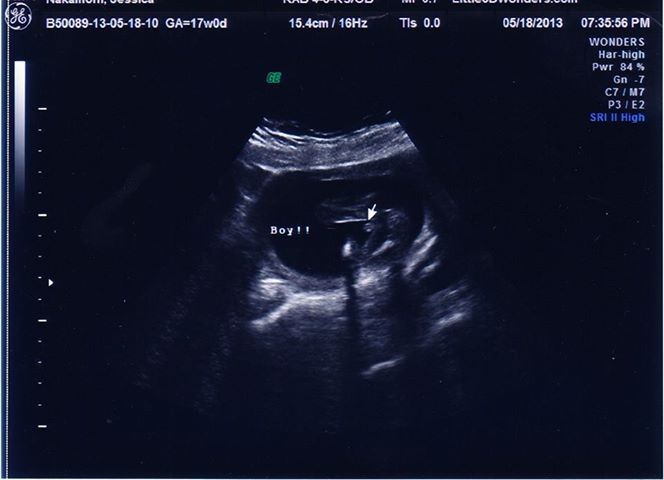

i went to another place to recheck gender... is this shot any better??![]()

I commented on in-gender but yes, much better

This one shows boy parts.

I didn't see the original pic...but this one looks very boy